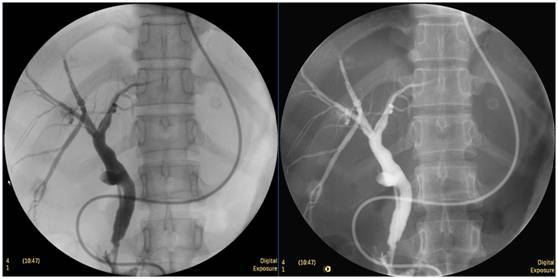

膽囊結(jié)石

ERCP膽囊顯影,見多枚結(jié)石影。

膽總管結(jié)石

柱狀球囊擴(kuò)張完全,膽總管擴(kuò)張,下段見充盈缺損影。

膽總管擴(kuò)張,下段見明顯充盈缺損(上圖為反片且局部放大后效果)